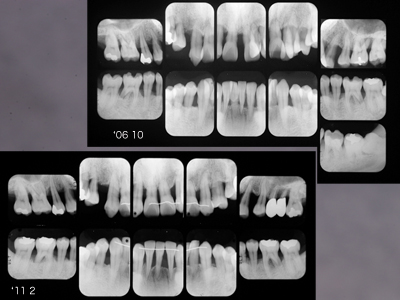

重症例の治療経過

以前ご紹介した重症例の初診時の正面観とデンタルです。

歯肉の激しい腫脹疼痛発熱のため摂食困難となり入院、点滴栄養補給された方です。

'08 9主治医の紹介で当院に来院されて以来、さすがに熱心にプラークコントロールに取り組んでいただきました。'08 9~'10 2のプロービングデプスの変化です。青は6mm以上、赤はBOPを示しています。

「PD6mm以上は歯周外科」というのがEBMだそうですが、EBMってのもあまりあてにならないことがわかります。そしてこの間の上下前歯部のレントゲン像の変化です。

初診時右上1左下1はすでにに根尖をこえて骨がないようにみえますが、1年半経過し骨が戻ってきました。抜歯の前に当院に来られて本当によかった。